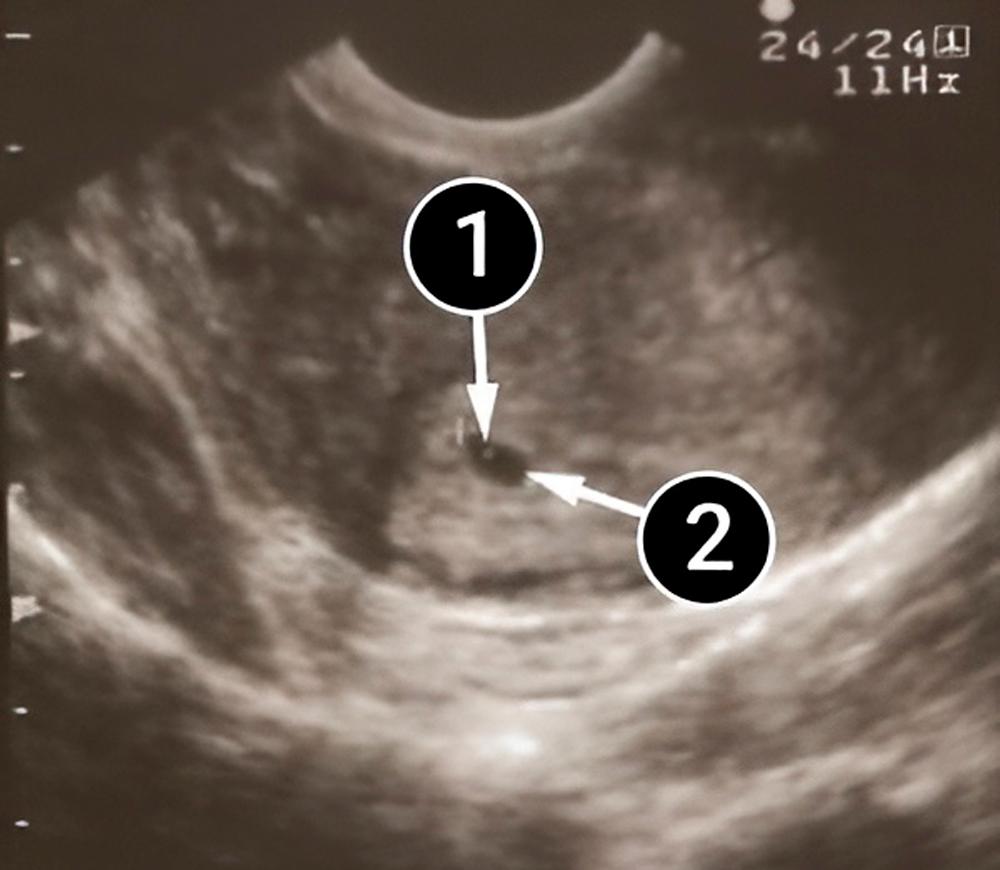

La siguiente fotografía muestra una vista longitudinal de un útero en forma de pera. Dentro de él se puede observar el saco amniótico, que es el pequeño óvalo negro. El contorno más claro que lo rodea es el endometrio. Las líneas de las paredes internas del útero siguen la misma forma de pera, creando un nido acogedor para el bebé.

útero

saco amniótico